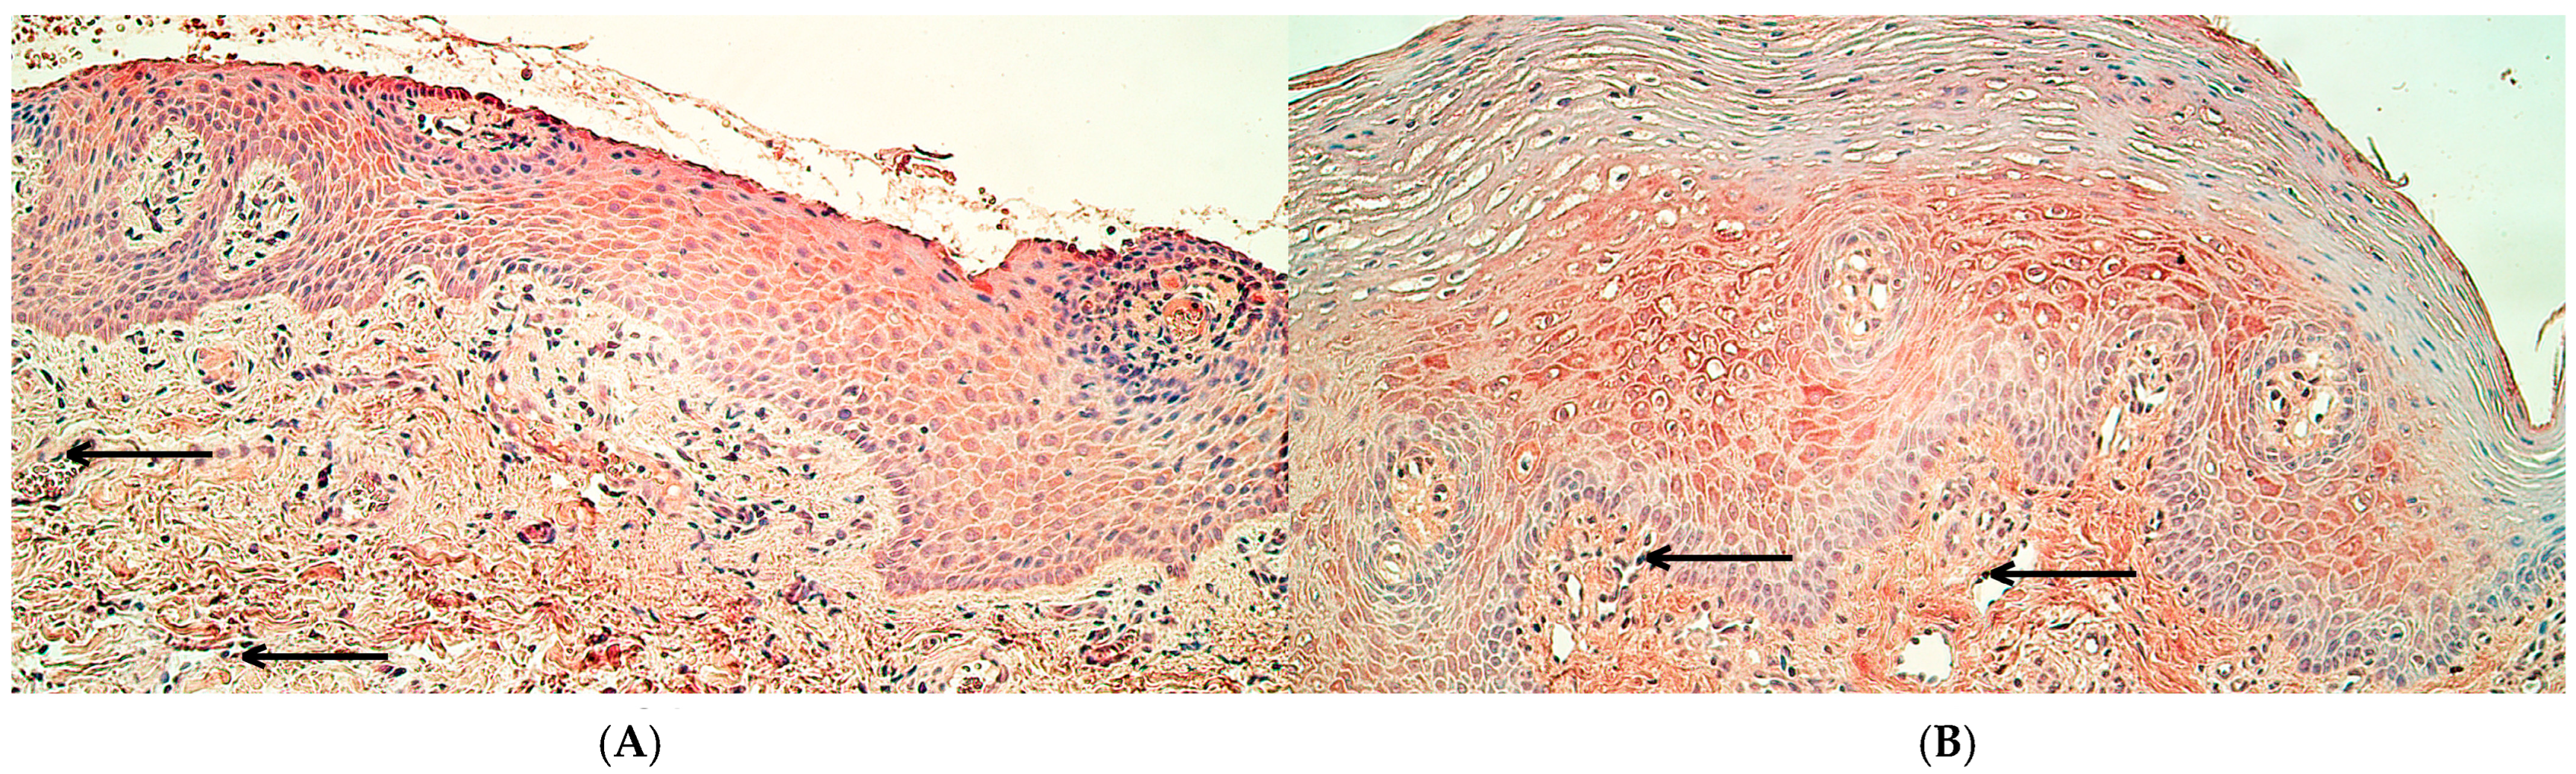

2.1. Immunohistochemistry

3.1. Immunoreactivity of MSX1, NFκB p65, and CCL4 Proteins Was Significantly Decreased in Cleft Lip Connective Tissue and Endothelium but Not in Surface Epithelium

3.2. RYK Protein Immunoreactivity Was Significantly Decreased Only in Cleft Lip-Affected Connective Tissue